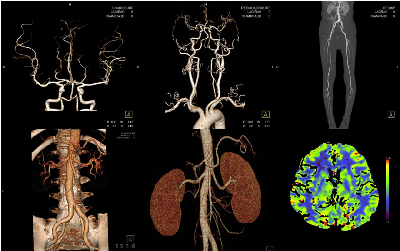

CT 혈관조영 – 혈관 ‘구조’를 보는 검사

✔ 혈관이 어디에서 얼마나 좁아졌는지

✔ 혈전, 석회화, 협착 위치 확인

✔ 수술·시술 전 계획에 필수

특징

- 검사 시간 짧음 (5~10분)

- 결과가 직관적

- 응급 상황에서도 사용 가능

< 주의 >

- 요오드 조영제 → 신장기능 체크 필요

- 방사선 노출 있음

ㅡ> 혈관 자체를 “지도처럼” 보고 싶을 때 선택

MRI 혈관조영 – 가장 정밀한 검사

✔ 혈관 + 신경 + 근육 + 연부조직 동시 평가

✔ 허리 통증, 신경압박, 혈관 문제 감별 필요 시

✔ CT로 설명 안 되는 통증일 때